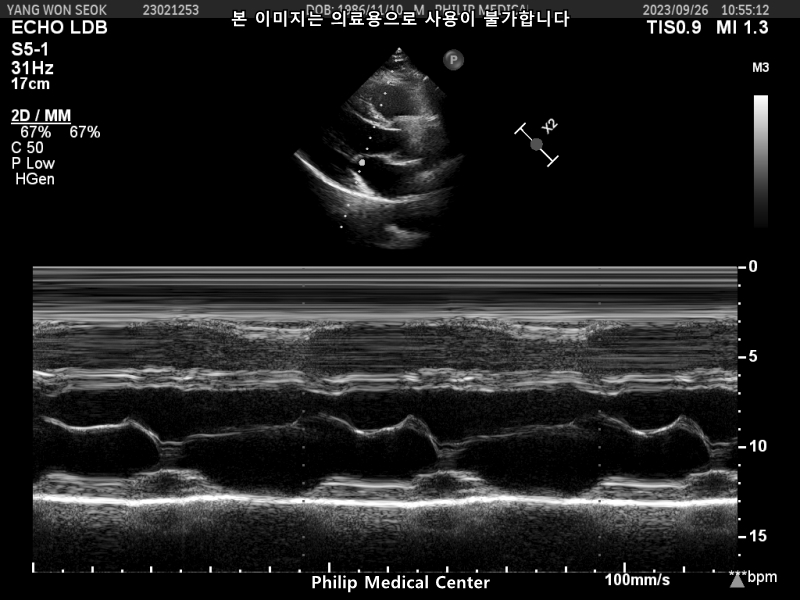

초음파 결과도 당장 큰 일은 아닐 듯 합니다

단지 경과 추적 관찰 및 예방적 치료 필요에 대해서는 내과와 상담하시는 것이 맞을 듯 합니다